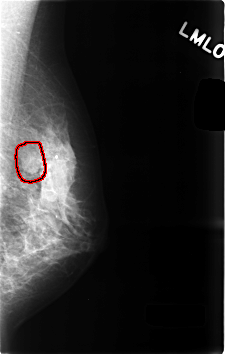

C_0494_1.LEFT_MLO

LEFT_MLO LINES 4592 PIXELS_PER_LINE 2920 BITS_PER_PIXEL 12 RESOLUTION 50 OVERLAY

FILE: C_0494_1.LEFT_MLO.OVERLAY

TOTAL_ABNORMALITIES 1

ABNORMALITY 1

LESION_TYPE MASS SHAPE OVAL MARGINS CIRCUMSCRIBED

ASSESSMENT 3

SUBTLETY 5

PATHOLOGY BENIGN

TOTAL_OUTLINES 1

BOUNDARY